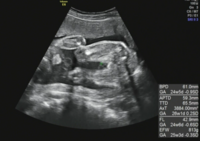

胎児の「大きめ」「小さめ」は、どのように判断するのか 胎児の大きさに差が出てくるのは、だいたい 妊娠週を過ぎた頃 からだ 1 16w1d胎児のBPDの大きさ 16w1dの健診で胎児のBPD、頭の大きさが384mmでした。 17 2 妊娠初期に胎嚢のみ。 症状もなく、不安です。Jun 17, 21 · 妊娠29週の胎児の体重や大きさは? 妊娠29週の胎児の大きさは約35~40cm、体重は約1,000~1,500gです(※1)。なかには1,500gを超えている子もいますが、この時期の胎児の成長には個人差があるので、妊婦健診のときに医師から特別な指導がなければ、小さめでも問題ありません。推定胎児体重だけではなく、各部位の計測値も含めて総合的に判断すること が大切です。 2) 超音波計測の実際 胎児の基本的な胎児計測断面と計測法を以下に示します。 ①・子宮内の観察 まず、胎児、羊水、胎盤の全体像を確認します。

生まれてくる前の我が子の記念写真 超音波胎児スクリーニングでわかること 東京ベイ 浦安市川医療センター